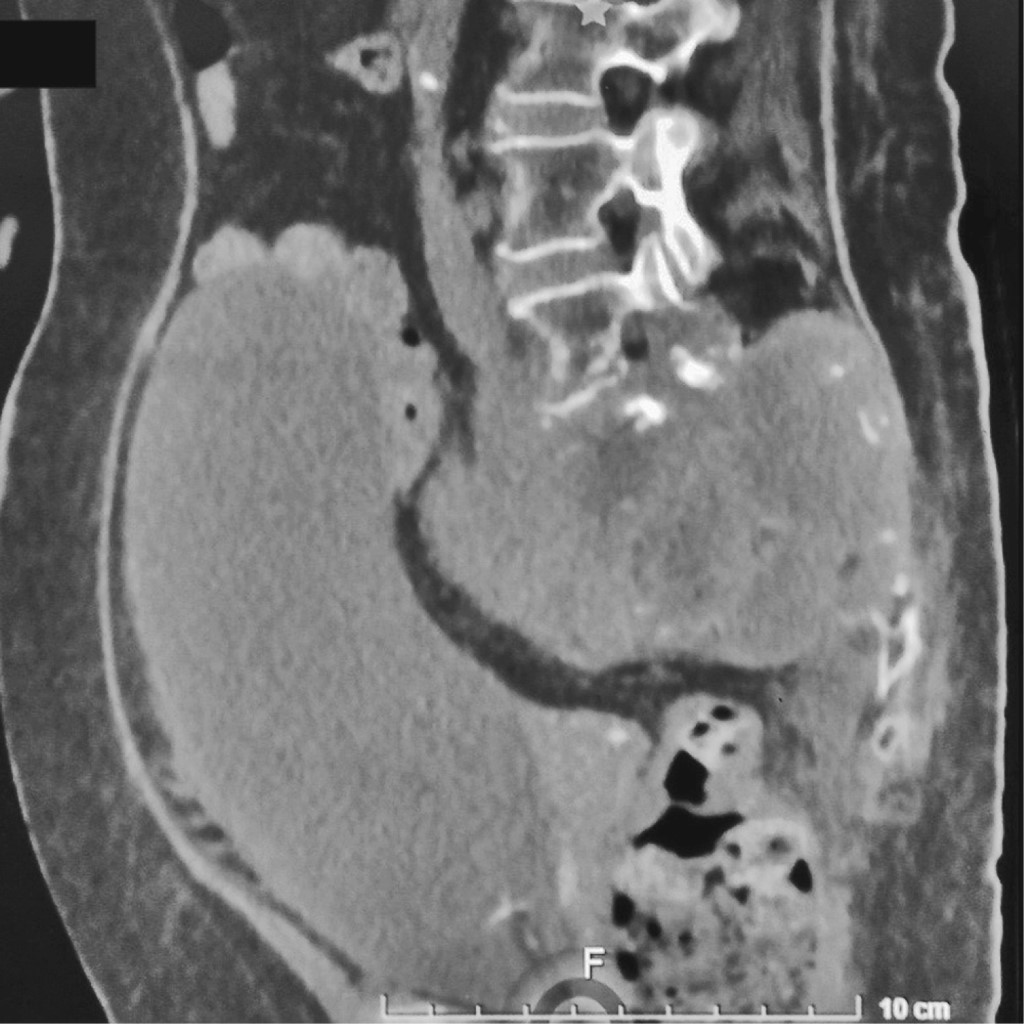

Sacral tumors are rare pathologies, but their management generally generates a complex medical problem. Different types of primary tumors can occur in the sacrum because of its peculiar embryogenic development. The diagnosis is difficult because of the lack of specific signs and symptoms. Most of the primary tumors of the sacrum are benign aggressive lesions or low grade malignancies.1 Sacral tumors are usually diagnosed in advanced stages with extended dimensions involving the sacral nerves and surrounding organs2 (Figure 1). In general, the response to chemotherapy and radiotherapy is not satisfactory for these tumors3,4 and surgical treatment is one of the most challenging fields in orthopedics and spinal surgery because of the complicated anatomy of the sacral site.2

Because of nonspecific symptoms and their insidious development, sacral tumors usually are discovered with advanced imaging studies. Plain radiography is often the first imaging modality performed; however, this often remains inefficient because of the difficulty in evaluating the sacrum on X-ray films2 (Figure 2). When an abnormality is detected in the sacrum on conventional radiographs or clinical suspicion warrants, cross-sectional imaging with computer tomography (CT) and magnetic resonance imaging (MRI) techniques, must be employed.

CT is an excellent tool to evaluate cortex integrity, to asses and characterize periosteal new bone formation, and to detect and characterize matrix mineralization; on the other hand, MRI is superior in soft tissue contrast resolution, which provides the ability to sensitively detect lesions, characterize tissue types, and accurately stage tumors locally for their anatomic extent in the bone and soft tissue10 (Figure 3). The combination of T1 and T2 weighted imaging is suitable for evaluating nerve root, muscle and visceral structure involvement.

Figure 1